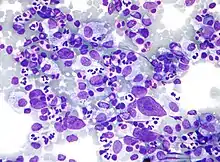

| Micrograph showing Hodgkin lymphoma (Field stain) | |

_mixed_cellulary_type.jpg.webp)

Microscopic examination of the lymph node biopsy reveals complete or partial effacement of the lymph node architecture by scattered large malignant cells known as Reed-Sternberg cells (RSC) (typical and variants) admixed within a reactive cell infiltrate composed of variable proportions of lymphocytes, histiocytes, eosinophils, and plasma cells. The Reed–Sternberg cells are identified as large often bi-nucleated cells with prominent nucleoli and an unusual CD45−, CD30+, CD15+/− immunophenotype. In approximately 50% of cases, the Reed–Sternberg cells are infected by the Epstein–Barr virus.[39]

Characteristics of classic Reed–Sternberg cells include large size (20–50 micrometres), abundant, amphophilic, finely granular/homogeneous cytoplasm; two mirror-image nuclei (owl eyes) each with an eosinophilic nucleolus and a thick nuclear membrane (chromatin is distributed close to the nuclear membrane). Almost all of these cells have an increased copy number of chromosome 9p/9p24.1.[40]